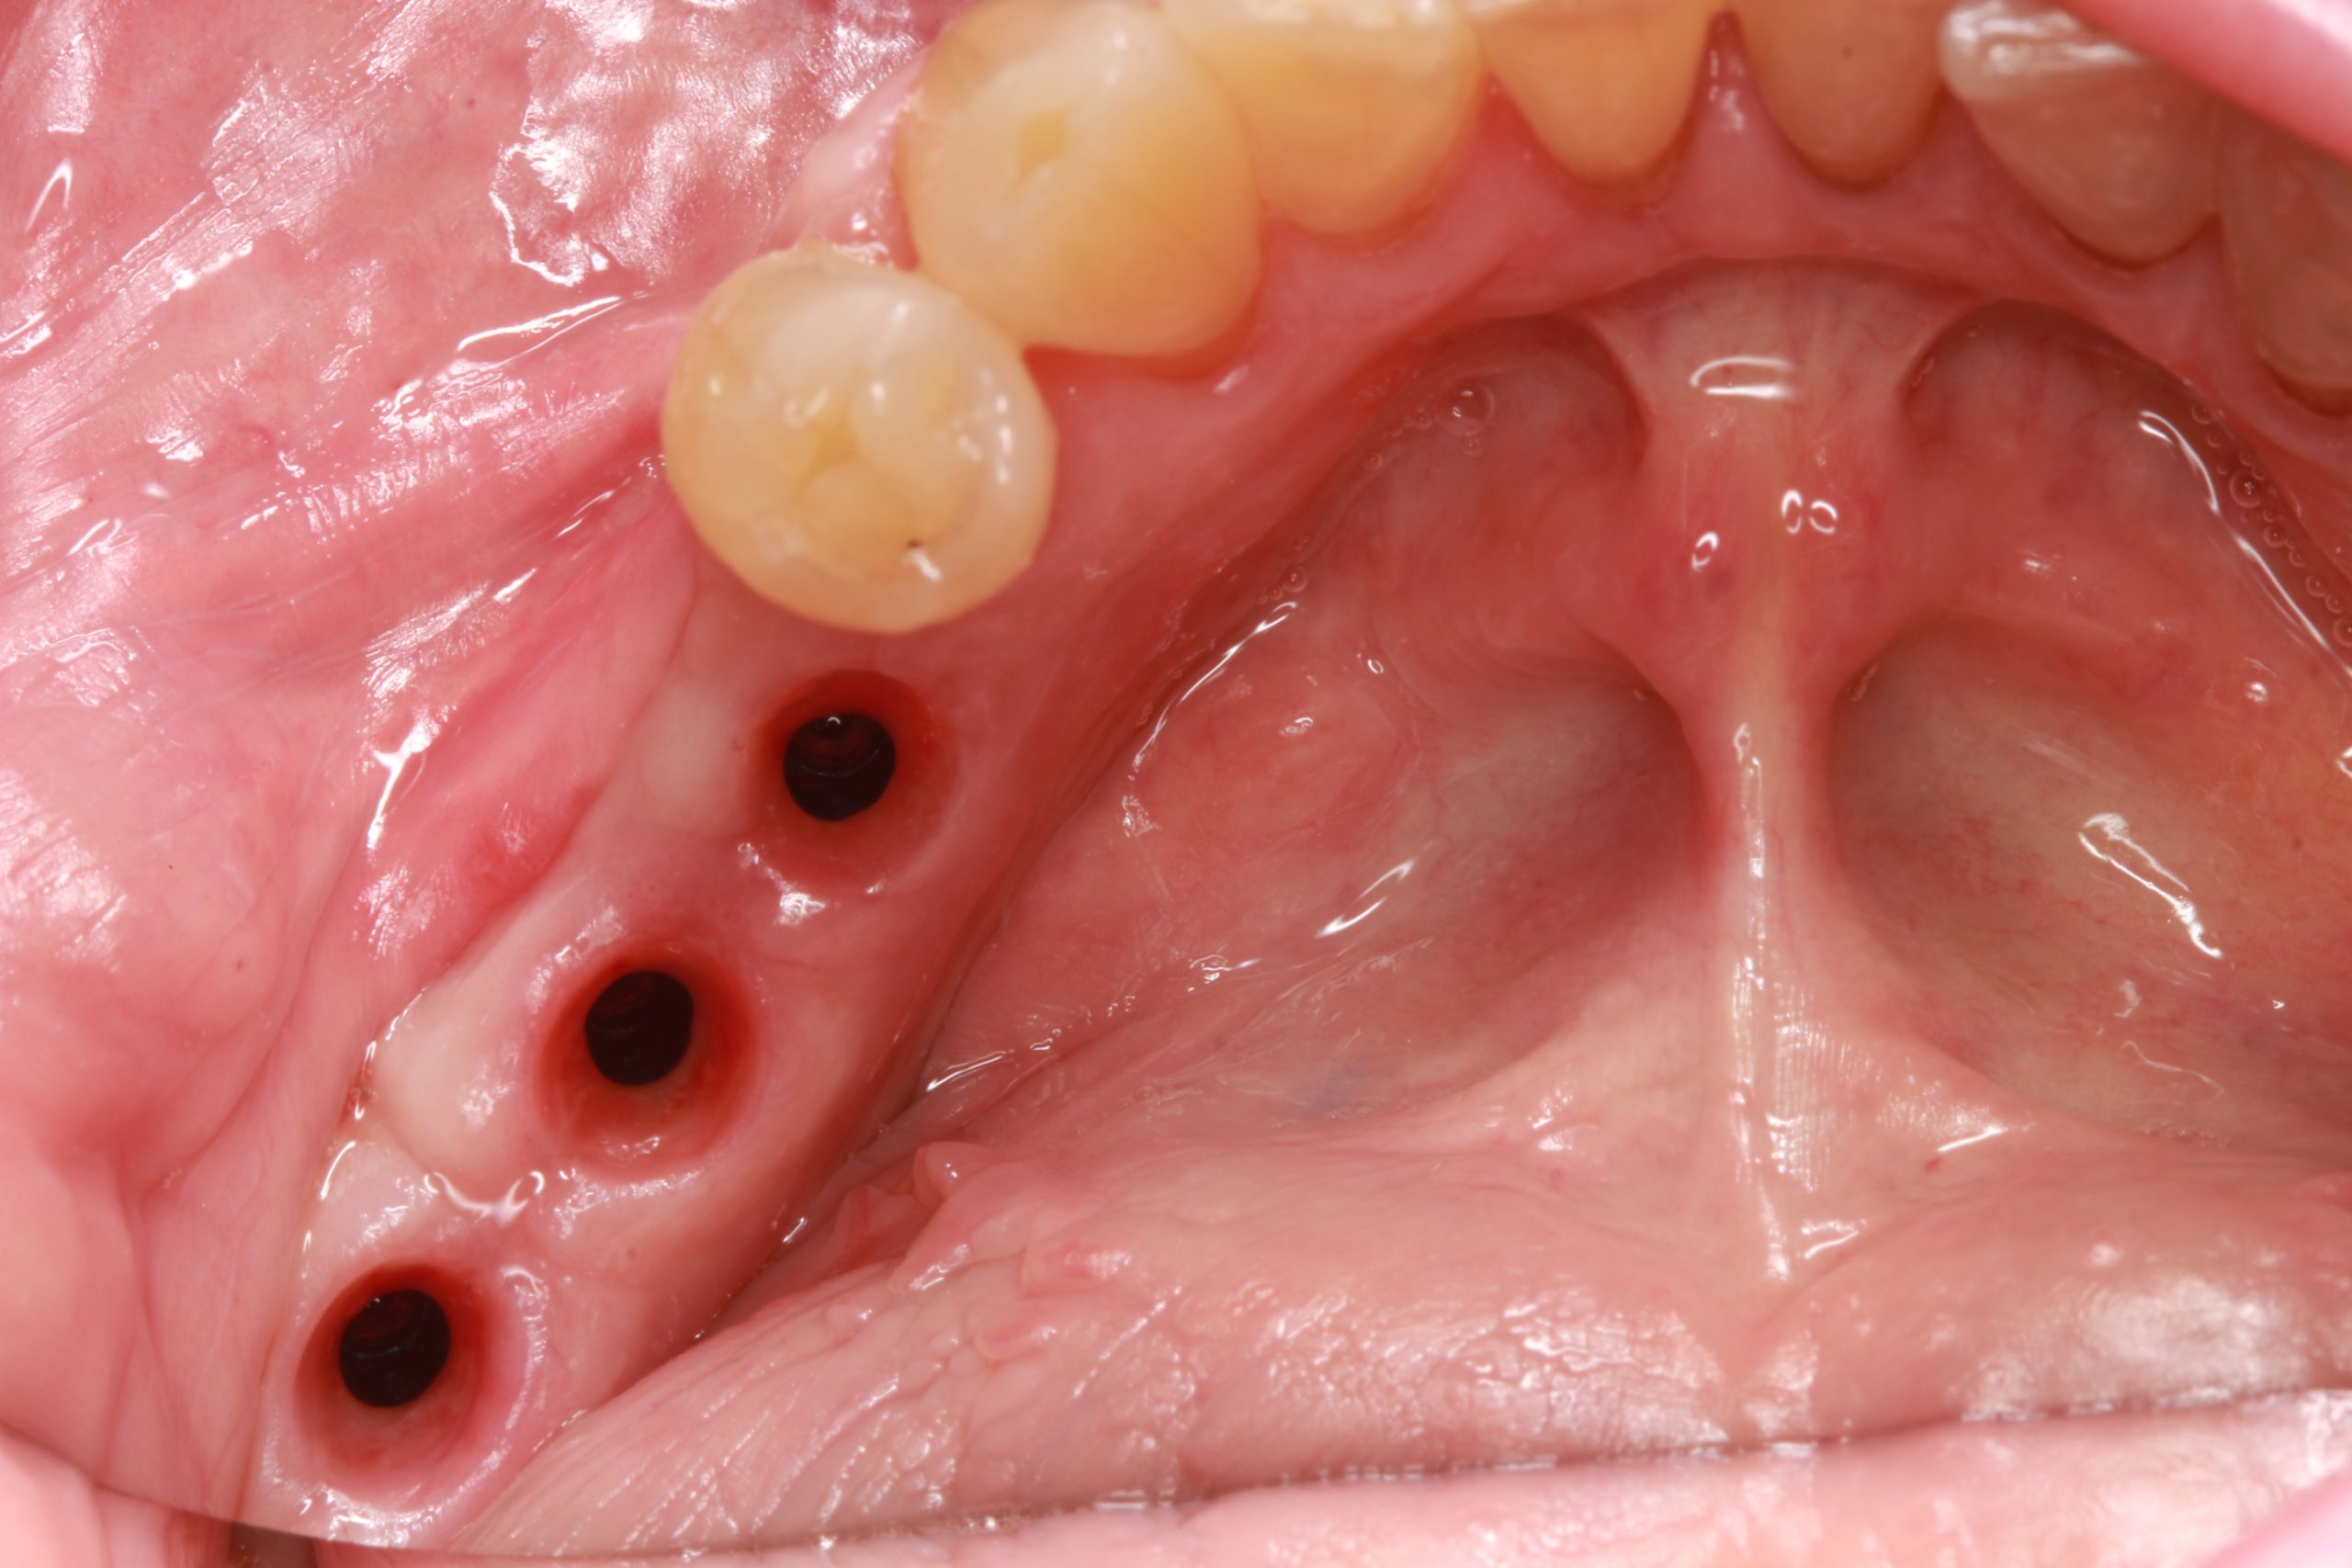

Nach drei Monaten wurden die Implantate freigelegt und der Abdruck gemacht.